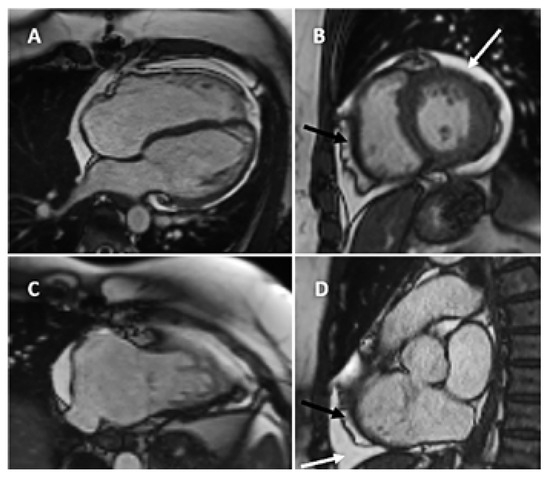

Cardiac magnetic resonance imaging (CMR) with cine, flow and tissue characterisation sequences excluded any disease of the parietal or visceral pericardium, right ventricular wall anomalies, myocardial oedema or relevant late gadolinium enhancement (Figure 3 and Figure 4), but confirmed a mild circular pericardial effusion without evidence of pericardial haematoma or myocardial rupture. Myocardial extracellular volume by native and post-contrast T1-mapping was normal with 24%. Qp/ Qs was 0.95 calculated by aortic flow and flow across the pulmonary trunk by phase contrast flow velocity mapping. A gated coronary angio-CT did not find any coronary artery fistula or anomalous communication.

Figure 3. CMR steady-state free precession cine still frames. (A) Four chamber view enddiastolic; (B) midventricular short axis; (C) RV 2-chamber view; (D) Right ventricular outflow tract with circular pericardial effusion (white arrow) and epicardial fat (black arrow).